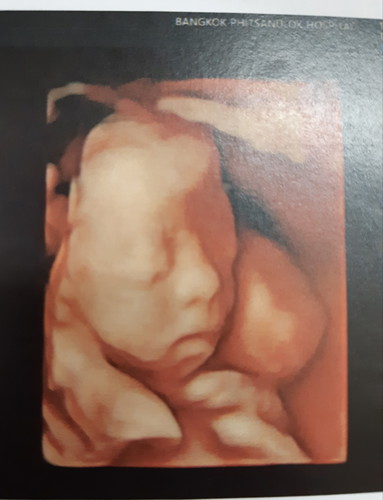

หนูนอนอยู่ในท้องแม่แม่ ยังหาวได้อีกอิอิ 23สัปดาห์จร้า